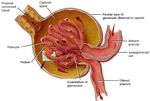

InsulinaLa Nefropatia Diabetica è quasi un «modello sperimentale» per testare l’effetto nefro-

protettivo dei farmaci bloccanti il R.A.S. Questi farmaci sono in grado di

ridurre la Pressione Idrostatica Intra-glomerulare contrastando l’ Iperfiltrazione

Glomerulare ed il passaggio di proteine attraverso la barriera glomerulare (Proteinuria)

ANGIOTENSINA II

FARMACI BLOCCANTI

IL R.A.S.SISTEMA RENINA-ANGIOTENSINA

(R.A.S.) Pro-renina

Angiotensinogeno β-bloccanti

Renina

Angiotensina I

ACE inibitori ACE

Inibitori

Chymase della RENINA

Angiotensina II

Antagonisti

Recettoriali

ARB

Recettore per

L’ Angiotensina II

Vasocostrizione Vasocostrizione Stimolazione alla

sistemica arteriole renali Sintesi di

(prevalentemente quelle efferenti) AldosteroneI Farmaci bloccanti il R.A.S. sono tanto più efficaci quanto